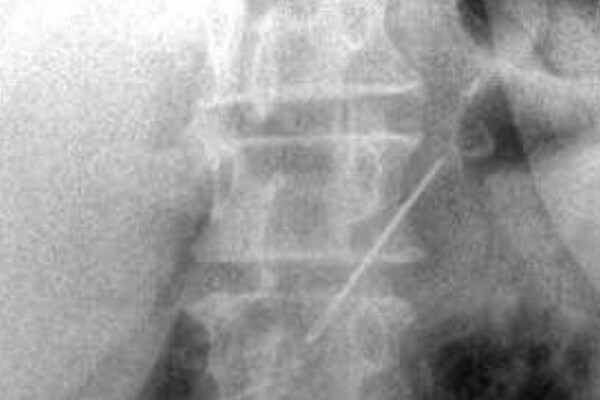

Пожилая женщина обратилась в Красногорскую больницу с жалобами на боли в животе. Пациентку обследовали и выяснили, что у нее в брюшной полости и одной передней брюшной стенке находятся четыре иглы.

Выяснилось, что женщина проглотила их около месяца назад — при каких обстоятельствах это случилось, не уточняется. За время нахождения в организме иглы успели обрасти тканями.

Медики провели пациентке лапаротомию и удалили все инородные предметы. Одна из игл проникла в поджелудочную железу, но орган все же удалось сохранить. Вмешательство прошло успешно.